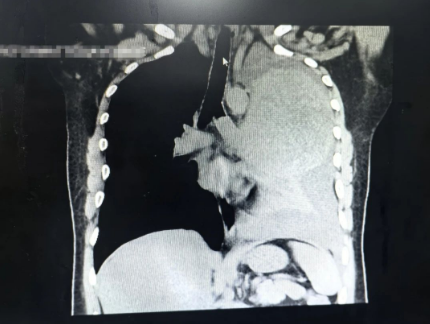

经多方打听,9月9日,麻先生慕名找到了北京天坛医院胸外科团队。胸外科副主任医师李维青说:“麻先生的肿瘤生长速度非常快,整个胸腔被肿瘤占据了一半。入院后第一时间为他复查CT,对比之前的8月的影像学检查,时隔不到一个月,肿瘤的直径由原来的11.9厘米增长到将近14厘米,体积几乎是翻倍了,”李维青被患者的肿瘤的生长速度给震惊了。考虑到患者情况不容乐观,李维青第一时间安排患者住院,完善检查、制定详细的治疗方案。

开胸骨、游离组织、分离静脉、阻断血管、切除肿物、探查气管缝合无漏气和出血……经过5个多小时的鏖战,无数次精准细致的操作,手术团队最终将占据患者左肺这颗将近19cm×16cm×10cm的巨大的肿物成功切除。